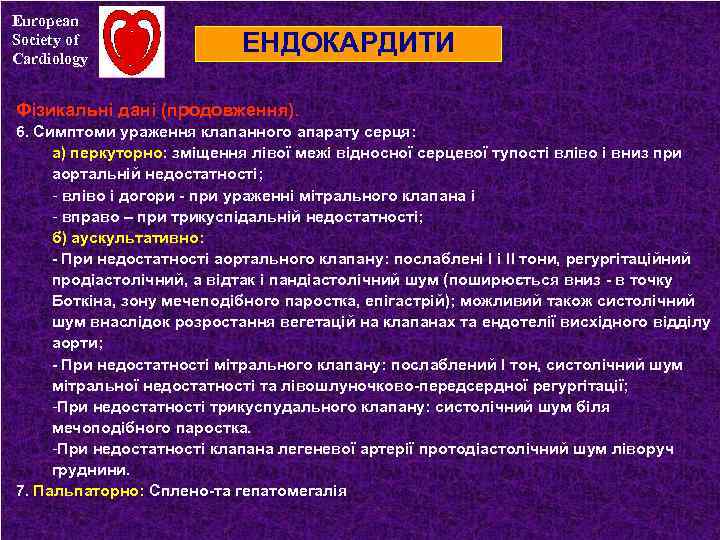

European Society of Cardiology ЕНДОКАРДИТИ Фізикальні дані (продовження). 6. Симптоми ураження клапанного апарату серця: а) перкуторно: зміщення лівої межі відносної серцевої тупості вліво і вниз при аортальній недостатності; - вліво і догори - при ураженні мітрального клапана і - вправо – при трикуспідальній недостатності; б) аускультативно: - При недостатності аортального клапану: послаблені І і ІІ тони, регургітаційний продіастолічний, а відтак і пандіастолічний шум (поширюється вниз - в точку Боткіна, зону мечеподібного паростка, епігастрій); можливий також систолічний шум внаслідок розростання вегетацій на клапанах та ендотелії висхідного відділу аорти; - При недостатності мітрального клапану: послаблений І тон, систолічний шум мітральної недостатності та лівошлуночково-передсердної регургітації; -При недостатності трикуспудального клапану: систолічний шум біля мечоподібного паростка. -При недостатності клапана легеневої артерії протодіастолічний шум ліворуч груднини. 7. Пальпаторно: Сплено-та гепатомегалія